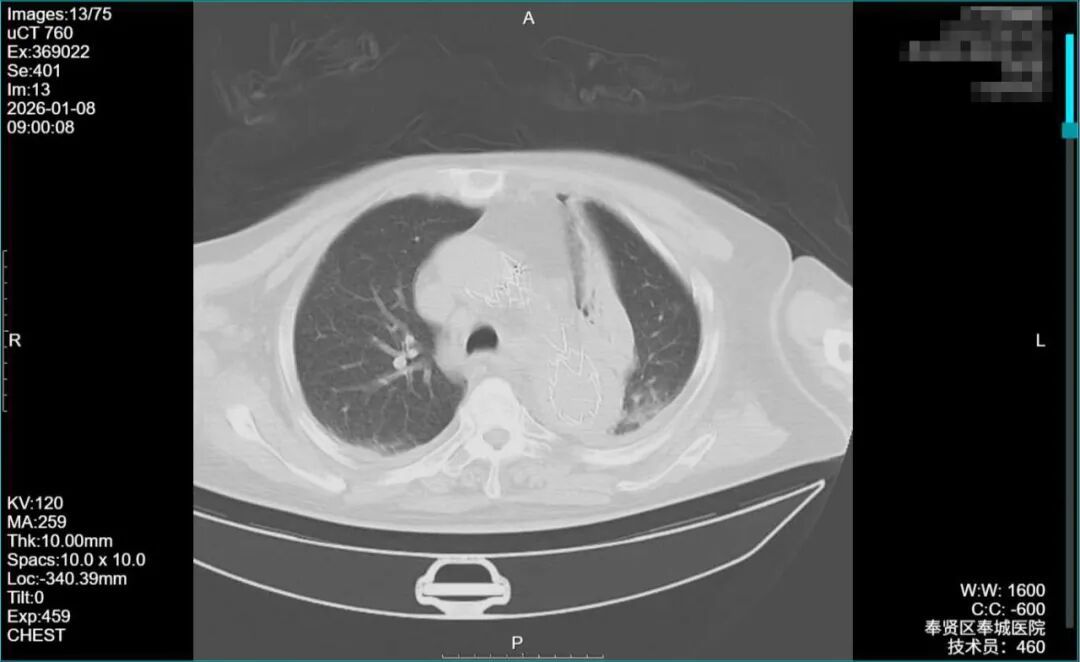

术后影像显示:覆膜支架定位精准,主动脉破口被完全隔绝,血管血流恢复正常!

手术成功只是第一步,术后监护同样关键。张爷爷被立即转入重症医学科(ICU),这里的医护团队早已严阵以待,展开全方位生命支持与监护:精准调控血压、监测胸腔引流、预防感染……每一个细节都做到极致。

在ICU团队的精心照料下,张爷爷的生命体征逐渐平稳,意识慢慢清醒,胸腔引流液逐日减少。几天后,他顺利转出ICU,进入普通病房。如今,老人已能正常交流,身体正在稳步康复中,家人握着医护人员的手连连道谢:“是你们没放弃,才给了老爷子第二次生命!”